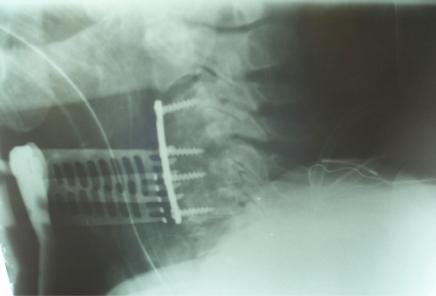

Dialysis-related spondyloarthropathy is a rare cause of spinal deformity and cervical myelopathy. Optimal management of cervical spine spondyloarthropathy often requires circumferential reconstructive surgery, because affected patients typically have both the anterior column and the facet joints compromised. The occasional presence of noncontiguous or "skip lesions" adds an additional level of complexity to surgical management, because decompression and fusion in an isolated segment of neural compression can worsen spine deformity by applying increased stress to adjacent cervical spine segments. We report two cases of hemodialysis patients who presented with cervical myelopathy and initially had anterior cervical discectomy or corpectomy. Because symptoms recurred due to hardware failure, both patients required posterior spine fusion as well. In retrospect, because of the hardware failure, both of these patients might have benefited from a circumferential (combined anterior and posterior) cervical spine reconstruction as their initial treatment.

透析相关性脊柱关节病是脊柱畸形和颈椎脊髓病的罕见病因。颈椎脊柱关节病的最佳治疗通常需要进行环形重建手术,因为受影响的患者通常前柱和小关节均受损。偶尔出现的非连续性或“跳跃性病变”增加了手术治疗的复杂性,因为在孤立的神经受压节段进行减压和融合会因对相邻颈椎节段施加更大压力而加重脊柱畸形。我们报告了两例血液透析患者,他们均表现为颈椎脊髓病,最初接受了颈椎前路椎间盘切除术或椎体次全切除术。由于内固定失败导致症状复发,两名患者均还需要进行后路脊柱融合术。回顾来看,由于内固定失败,这两名患者最初若接受环形(前后联合)颈椎重建术可能会受益。